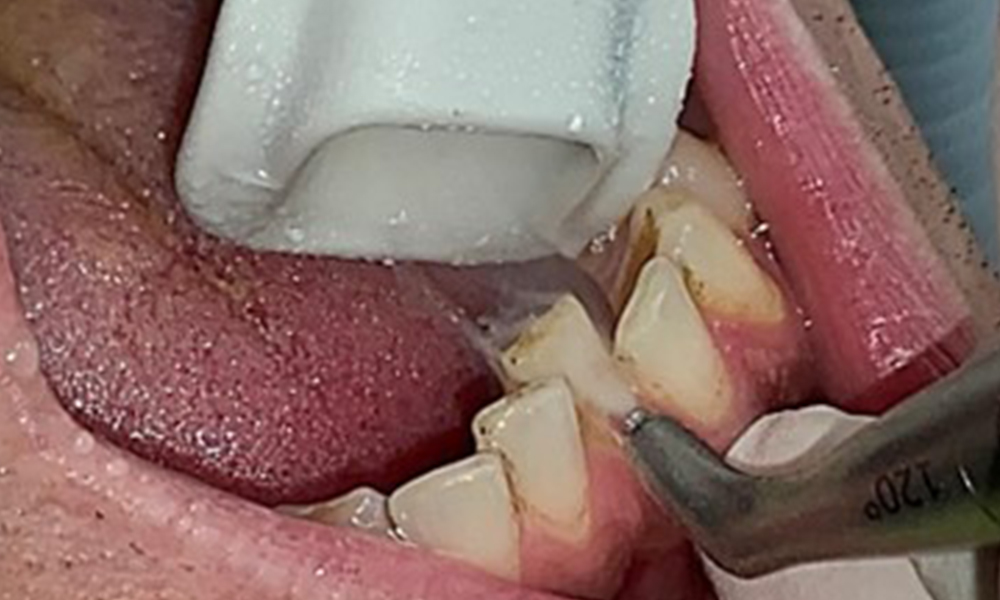

Discolouration caused by nicotine and tea consumption can be removed easily using an air polisher (Fig. 11).

Air polishing system use in the mandibular frontal lingual area (here, Proxeo Aura, W&H)

Fig. 11 Air polishing system use in the mandibular frontal lingual area (here, Proxeo Aura, W&H), © Dr R. Krapf

When using more abrasive powder, it is essential to work from a cervical to coronal direction and never point the outlet nozzle towards the gingiva to prevent potential emphysema. Good suction on the contralateral side is essential to reduce aerosol formation (Fig. 12).

Use of the air polishing system away from the sulcus with contralateral suction

Fig. 12 Use of the air polishing system away from the sulcus with contralateral suction, © Dr R. Krapf